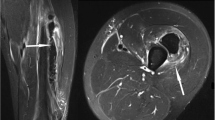

On ultrasound, contusion is characterised by discontinuity of normal muscle architecture, with ill-defined hyperechogenicity that may cross fascial boundaries [37]. MR imaging varies according to severity of injury, but typically there is a feathery appearance of diffuse muscle oedema on STIR and FS T2-w images [1] (Fig. 8). Increased muscle girth can be observed but there are no other architectural changes, such as fibre discontinuity or laxity. In case of severe trauma with muscle fiber disruptions, deep intramuscular haematoma is seen [3] (Fig. 9). Signal intensity within the haematoma is influenced by the concentration of protein, methaemoglobin, magnetic susceptibility at high field strength, and tissue clearance [42]. Acute haematomas (<48 h) are typically isointense on T1-w images, and subacute haematomas (<30 days) appear hyperintense relative to muscle on both T1-w and fluid-sensitive sequences secondary to methaemoglobin accumulation [28]. As the haematoma evolves, a wide range of MR signal intensity can be seen within the collection, depending on the age of degradation products. Chronic haematoma characteristically shows a rim of hypointensity on all pulse sequences due to haemosiderin. As blood degradation products get reabsorbed over a course of 6–8 weeks, the size of haematoma will decrease [30].

A 22-year-old rugby player presenting with stiffness of the right thigh after receiving a direct blow to the right anterior thigh during a tackle. a Sagittal and (b) axial STIR images show diffuse intramuscular hyperintensity, consistent with contusion injury of the rectus femoris, vastus lateralis and vastus intermedius muscles. Epifascial haematoma is noted superficially. The sagittal image demonstrates the longitudinal extent of the contusion injury and the haematoma

A 21-year-old football player presenting 5 days after a direct contusion injury to the left anterior thigh. a Coronal fat-suppressed (FS) T2-w TSE image reveal severe contusion injury of the vastus intermedius muscle, which extends to the proximal part of the musculotendinous junction of the quadriceps. The lesion is located at the middle part of the muscle and measures about 11 cm in long axis. The fluid-equivalent portion of the lesion represents a deep intramuscular haematoma. b Axial FS T2-w TSE image shows an additional strain of the rectus femoris muscle without a tear, depicted as hyperintensity surrounding the central musculotendinous junction at the mid-portion of the muscle (arrow)